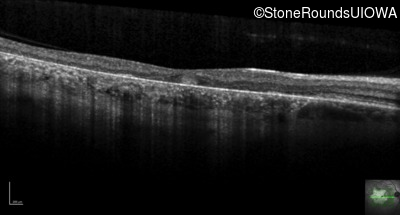

Optical Coherence Tomography - Left - 20/20 -2

Exemplar / OCT Stack